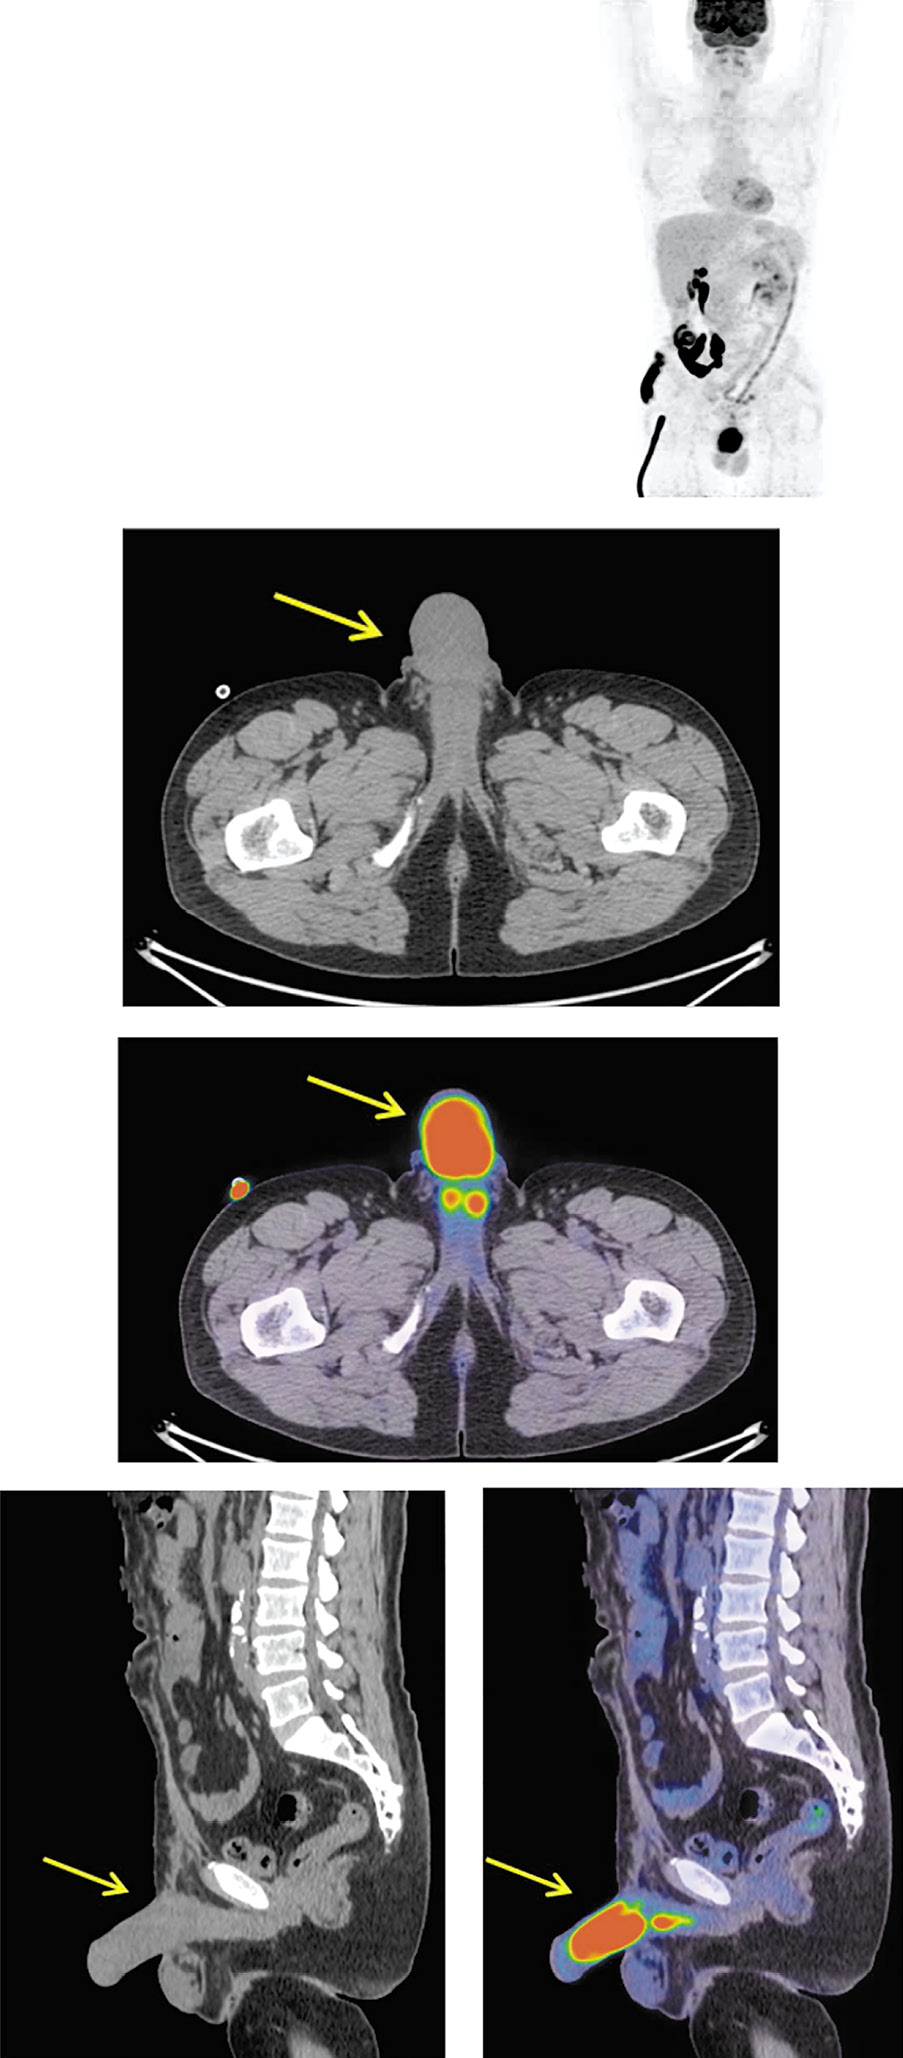

Пациенту выполнена позитронно-эмиссионная томография, совмещенная с компьютерной томографией (ПЭТ/КТ), с 18-фтордезоксиглюкозой (ФДГ). На MIP, аксиальной и сагиттальной КТ и ПЭТ/КТ-проекциях в кавернозных телах полового члена с двух сторон, ближе к корню полового члена, на протяжении до 33 мм отмечается симметричная фиксация радиофармпрепарата (РФП), коэффициент максимального стандартизированного накопления SUVmax составил 9,82. Другая зона повышенной фиксации РФП циркулярного характера обнаружена на протяжении кавернозных тел в дистальном направлении, длиной до 80 мм, SUVmax 12,44 с признаками приапизма (рис. 1).

Рис. 1. Пациент Е., 49 лет. На MIP, аксиальной и сагиттальной КТ, ПЭТ/КТ проекциях в кавернозных телах полового члена, с двух сторон, ближе к корню, отмечается симметричная фиксация РФП на протяжении до 33 мм, SUVmax 9,82. В дистальном направлении отмечается зона повышенной фиксации РФП циркулярного характера на протяжении до 80 мм, SUVmax 12,44 с признаками приапизма.